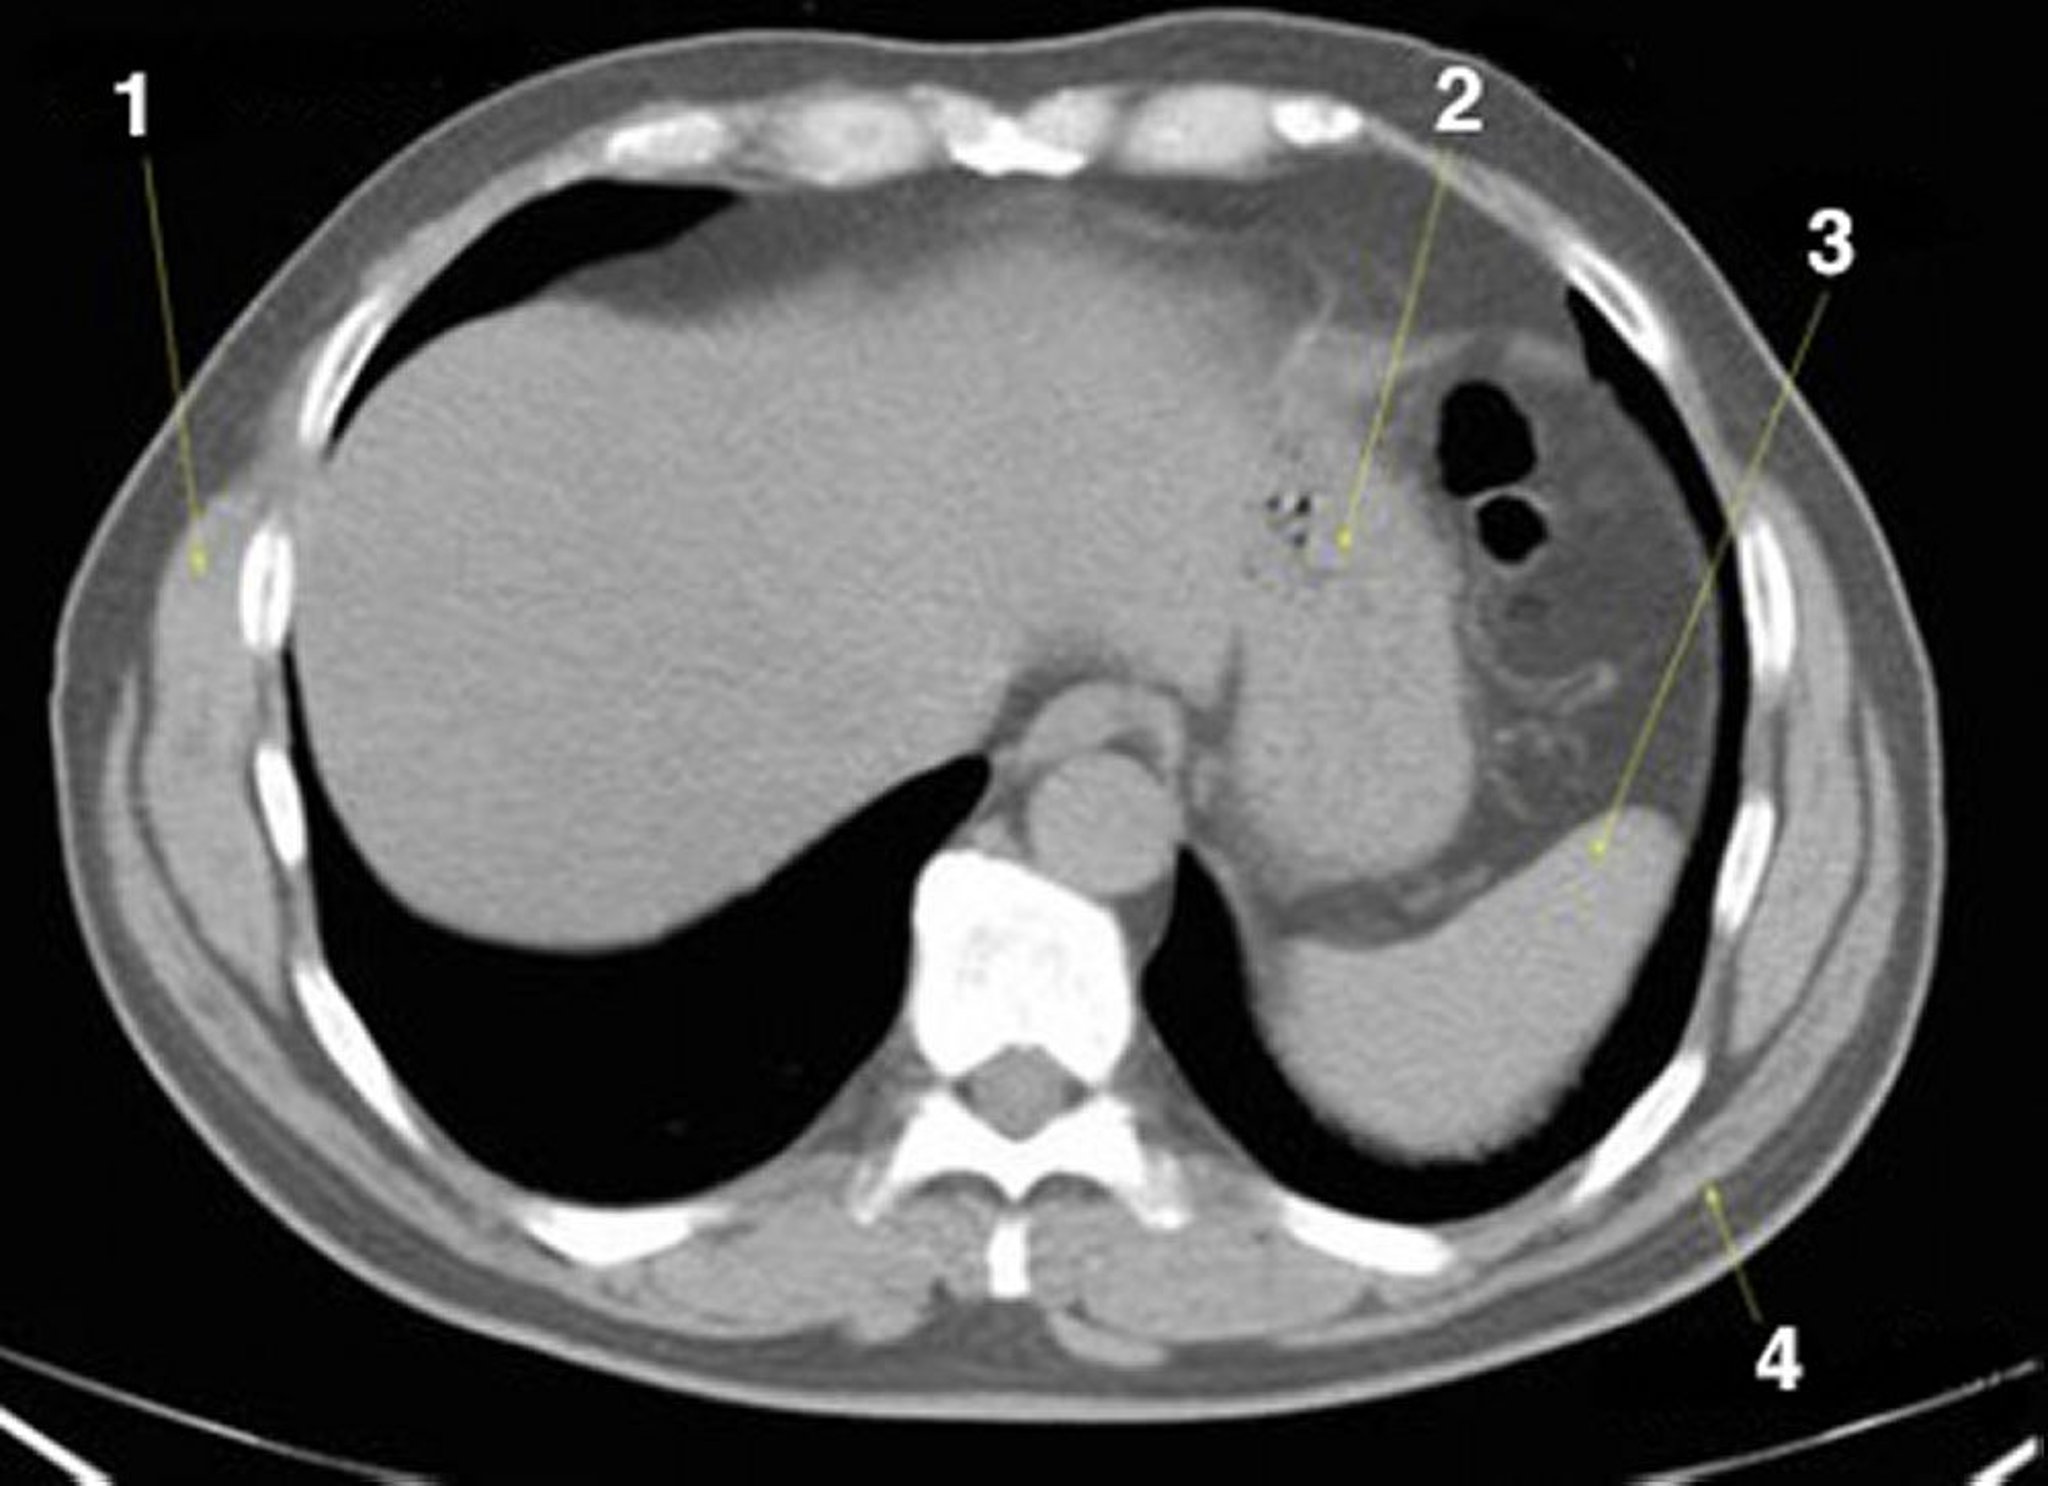

Phim chụp CT vùng bụng và vùng chậu không thuốc cản quang cho thấy giải phẫu bình thường (lát cắt 2)

1 = cơ răng trước; 2 = dạ dày; 3 = lách; 4 = cơ lưng rộng.